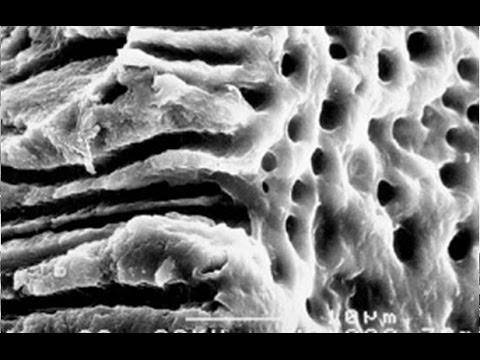

Эндодонтический материал «Белодез-Активатор» производства ВЛАДМИВЫ понижает коэффициент поверхностного натяжения жидкостей для химического расширения и жидкостей для антисептической обработки корневых каналов зубов, увеличивает смачивающую способность ирригантов, обеспечивает их проникновение в труднодоступные участки системы корневых каналов и в дентинные канальцы, образует пену для лучшего удаления дентинных опилок и органических остатков из системы корневых каналов. «Белодез-Активатор» образует прозрачный раствор в сочетании с эндодонтическими ирригантами, содержащими гипохлорит натрия («Белодез»), ЭДТА («ЭндоЖи №2») или хлоргексидина биглюконат («Белсол №2»).